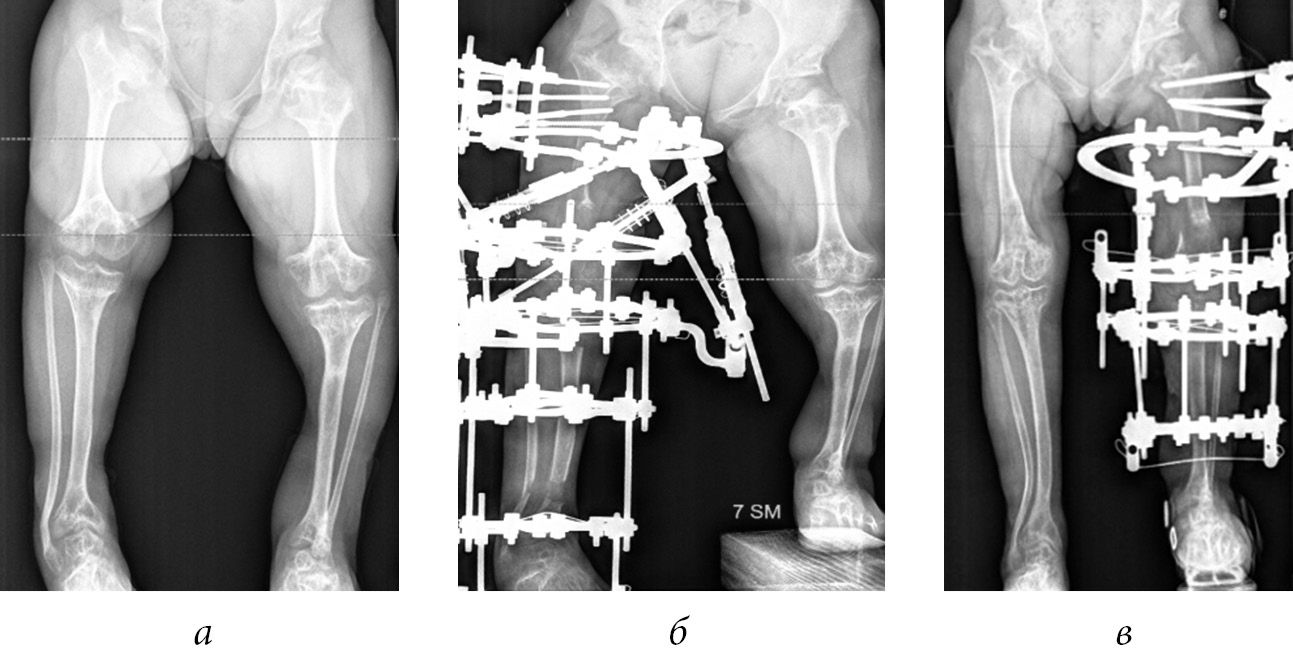

In our series of cases, in 8 out of 12 (66.7%) patients, we noted lesion to the proximal growth zones of the femoral bone with the formation of varus deformities of the necks, which necessitated surgical correction (Fig. 4).

Fig. 4. Radiographs of the hip joints of patients K. (a) and A. (b) with varus deformities of the femoral necks